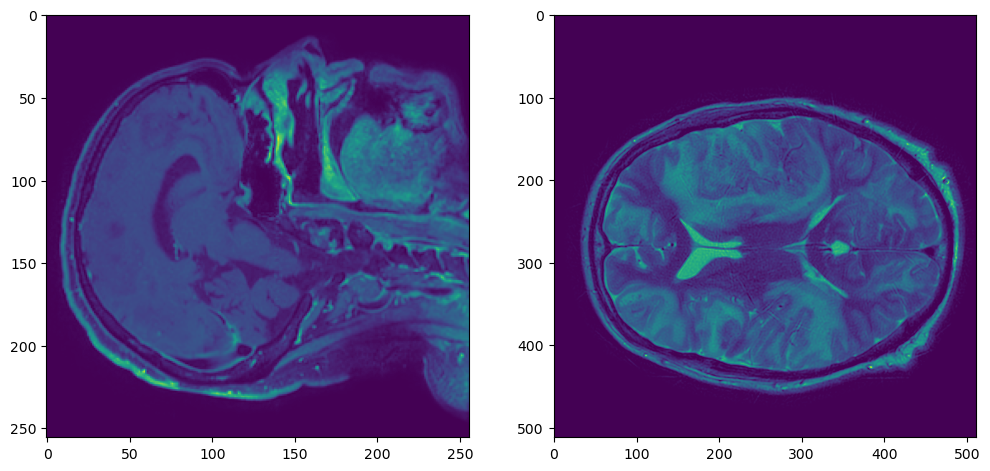

%%time

t1_resampled = resample(t1_sitk, t2_sitk)

t2_sitk_array = sitk.GetArrayFromImage(t2_sitk)

t1_resampled_array = sitk.GetArrayFromImage(t1_resampled)

plt.figure(figsize=(12,6))

plt.subplot(121)

plt.imshow(t2_sitk_array[t2_sitk_array.shape[0]//2,:,:])

plt.subplot(122)

plt.imshow(t1_resampled_array[t1_resampled_array.shape[0]//2,:,:])

t2t1resampled

Работает гораздо быстрее: